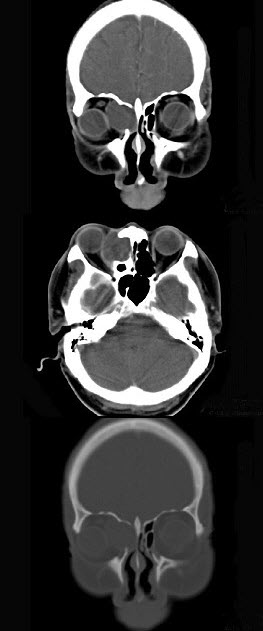

- 多项选择题女性38岁,右侧眼球运动障碍伴眼球突出4个多月,CT扫描如图,请选择正确的描述和答案()。

A、右侧筛窦内可见囊性肿块影,边缘光整

B、囊性肿块向右侧眼眶内突入,压迫内直肌

C、右侧眶内壁呈受压变薄、断裂

D、考虑为右侧筛窦黏液囊肿

E、考虑为筛窦癌

- A,B,C,D